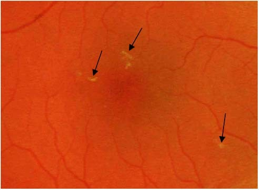

硬性渗出

硬性渗出样例,如箭头所示。其他区域视网膜上更深位置的较暗的黄白色小点是玻璃膜疣,不是硬性渗出。

硬性渗出(HE)是视网膜上的小的白色或黄白色、边界清晰的的沉着物。通常呈现为“蜡状”,闪亮或有光泽。

硬性渗出通常位于视网膜外层,但可能会更偏表面,尤其是在视网膜水肿存在的情况下。硬性渗出可以是独立的小点,也可以是连续的片状斑点,或围绕在视网膜水肿或微血管瘤周围的呈环状病变。在局部视网膜增厚的区域内,融合的硬性渗出可出现在视网膜外层或视网膜下。

注意:硬性渗出(HE)须与玻璃膜疣(一种常见的年龄相关性病理改变)相区分。

玻璃膜疣是在布氏膜(Bruh’s membrane)上,位于视网膜色素上皮之下,位置较深,呈扁平黄白色点状,有时还环绕着一圈细线状色素。

以下特征可用于区分这两种病变:

1)玻璃膜疣表面黯淡无光,而硬性渗出则呈闪亮蜡状。

2)玻璃膜疣常有淡化的色素边界,而硬性渗出则没有。

3)玻璃膜疣通常呈圆形,而硬性渗出通常为不规则形状。

4)玻璃膜疣通常广泛分散在各处或聚集在黄斑中心,而硬性渗出常出现在微血管瘤旁边或出现在视网膜水肿的区域内或边缘上。

5)黄斑区的玻璃膜疣常常大小不一,形态各异,但很容易地根据它们的数量、大小、颜色、位置,以及与视网膜水肿区域的相关性将其与硬性渗出区分开来。

6)小的玻璃膜疣有时可能会与小点状的硬性渗出相混淆。在这种情况下,立体眼底影像观察非常重要。玻璃膜疣位于视网膜色素上皮下,而硬性渗出通常位于视网膜内。